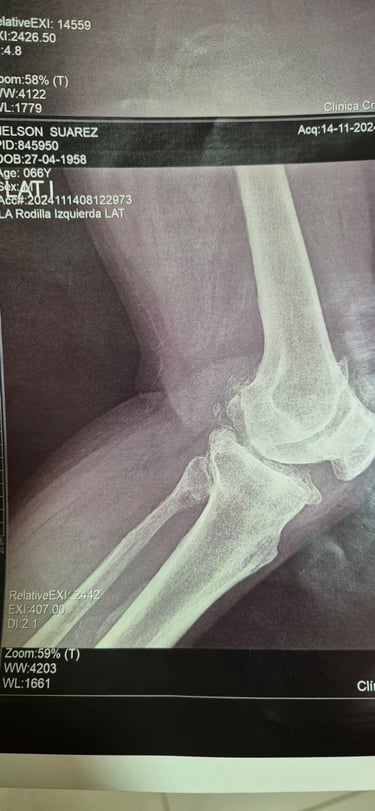

Cirugía de rodilla

Lesiones de meniscos y ligamentos (como LCA en rodilla)

Gallery

Provide a short description of the gallery, highlighting key things.